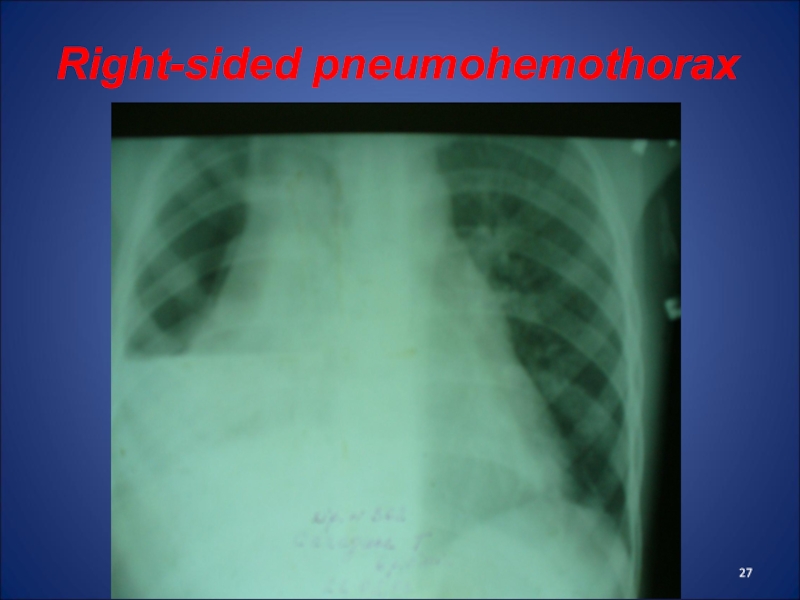

Слайд 27Right-sided pneumohemothorax

Right-sided pneumohemothorax

Слайд 26Pneumohemothorax

accumulation of blood and air in the pleural cavity, coming

from damaged lungs, vessels and bronchus

Clinic: rapid weak pulse, tachypnea,

decreased AP, pale skin, pain in the affected side of the chest, cough, shortness of breath.

Percussion - dull sound in the lower departments and tympanitis - in the upper, auscultation - missing or weakened breathing.

Treatment of pneumohemotorax: imposition of drainage on Bulau in 6-7 intercostal space, haemostatics, infusion and antibiotic therapy.

Pneumohemothoraxaccumulation of blood and air in the pleural cavity, coming from damaged lungs, vessels and bronchusClinic: rapid